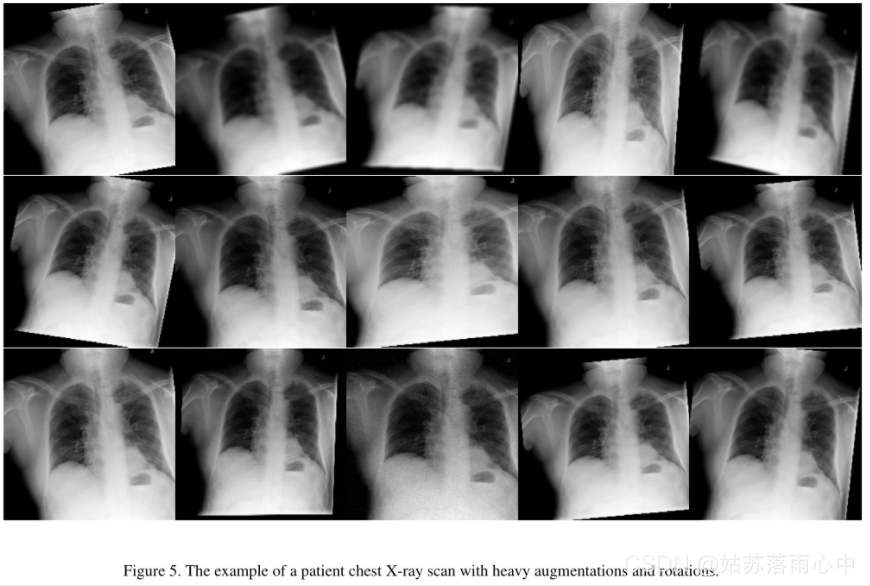

图像数据预处理与图像增强

原始图像按比例缩放为512×512像素分辨率,由于原始的挑战数据集不是很大,因此采用了以下图像增强来减少过拟合:轻微旋转(最多6度);移位,缩放,剪切;水平翻转;对于某些图像,模糊处理,添加噪声,进行伽玛值随机变化;有限提高亮度/伽玛增强量等。